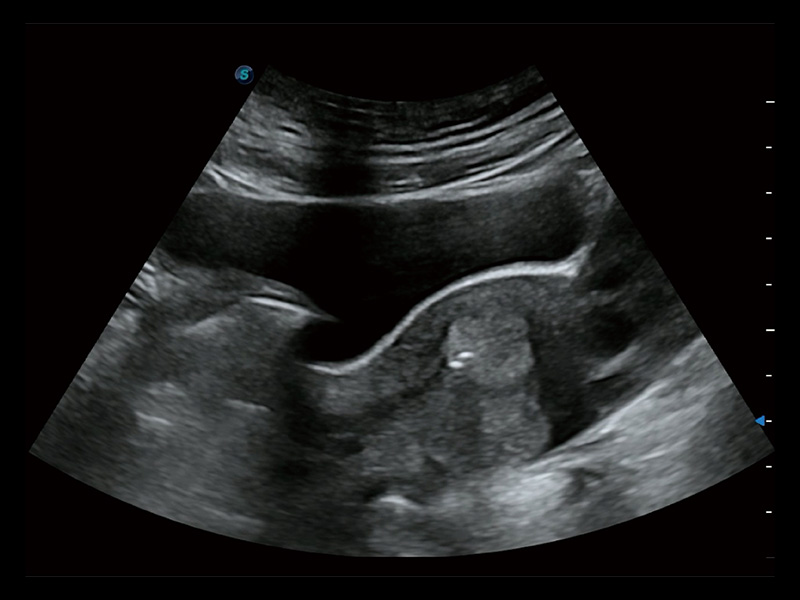

临床图

超声引导下双侧卵巢穿刺取卵